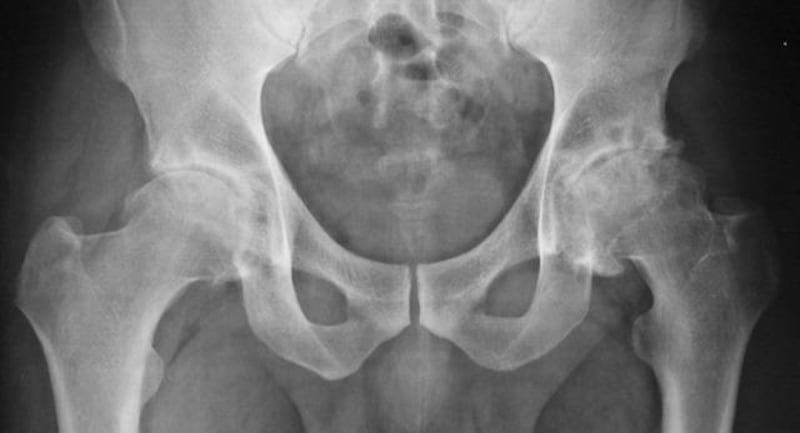

- Trasplantes de órganos de cerdo: aunque la primera que reseñamos no salió bien después de todo, se logró realizar, en principio, con éxito. Entonces, esto ha sido lo realmente importante que el cuerpo humano no rechazó el órgano de un animal y logró funcionar exactamente dos meses hasta su deceso.